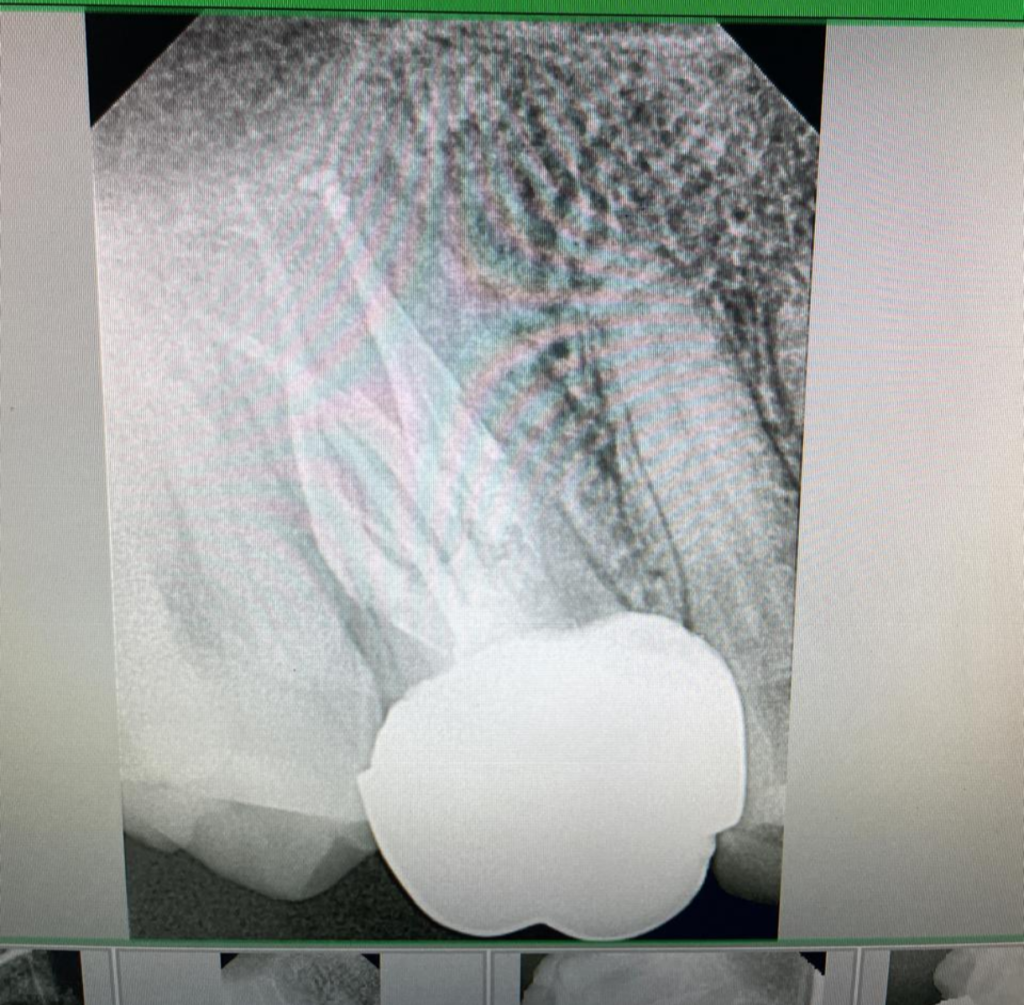

DOCTOR IN ACTION

Bilateral 6 canals in maxillary molars